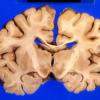

6A2 Wernicke's Dz (A27644) 1 copy

6A3 Wernicke's Dz (A27644) 1 copy